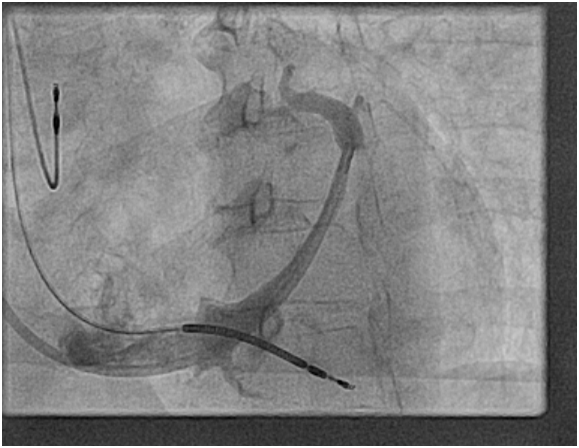

We admitted the patient, urgent interrogation of the device and changed in to (RV paced only) mode, with cessation of the abdominal twitches and the patient was completely comfortable and asymptomatic. Given she had significant symptomatic relief from shortness of breath after implantation we booked her for reposition of LV lead in the EP lab, balloon angioplasty of the coronary sinus lateral vein branch was done successfully and the lead was placed in a nice basal lateral position (Figures 3) (Figure 4). Then interrogation of CRTD with optimal results and normal post operative CXR (Figure 5).

Figure 4 Balloon angioplasty of the coronary sinus lateral vein branch was done successfully and the lead was placed in a nice basal lateral position.

Figure 5 Interrogation of CRTD with optimal results and normal post operative CXR.